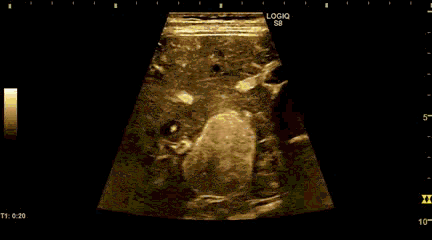

Quieres ver un ejemplo de cómo actual el contraste ecográfico en tiempo real:

En la imagen ves una lesión hepática que se vuelve brillante en su totalidad debido al contraste ecográfico.

In the image you see a liver injury that becomes bright in its entirety due to ultrasound contrast.